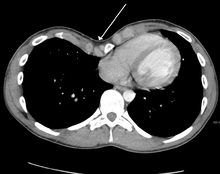

Because the heart is located behind the sternum, and because individuals with pectus excavatum have been shown to have visible deformities of the heart (seen both on radiological imaging and after autopsies), it has been hypothesized that there is impairment of function of the cardiovascular system in individuals with pectus excavatum. While some studies have demonstrated decreased cardiovascular function in pectus excavatum, there has been no consensus reached based on newer physiological tests (such as echocardiography) of the presence or degree of impairment in cardiovascular function in people with pectus excavatum. Similarly, there is no consensus on the degree of functional improvement after corrective surgery;[1] a 2013 meta-analysis yielded conflicting results.[16]

Many scales have been developed to determine the degree of deformity in the chest wall. Most of these are variants on the distance between the sternum and the spine. One such index is the Backer ratio which grades severity of deformity based on the ratio between the diameter of the vertebral body nearest to xiphosternal junction and the distance between the xiphosternal junction and the nearest vertebral body.[19] More recently the Haller index has been used based on CT scan measurements. An index over 3.25 is often defined as severe.[20] The Haller index is the ratio between the horizontal distance of the inside of the ribcage and the shortest distance between the vertebrae and sternum.[21]

Chest x-rays are also useful in the diagnosis. The chest x-ray in pectus excavatum can show an opacity in the right lung area that can be mistaken for an infiltrate (such as that seen with pneumonia).[22] Some studies also suggest that the Haller index can be calculated based on chest x-ray as opposed to CT scanning in individuals who have no limitation in their function.[23]